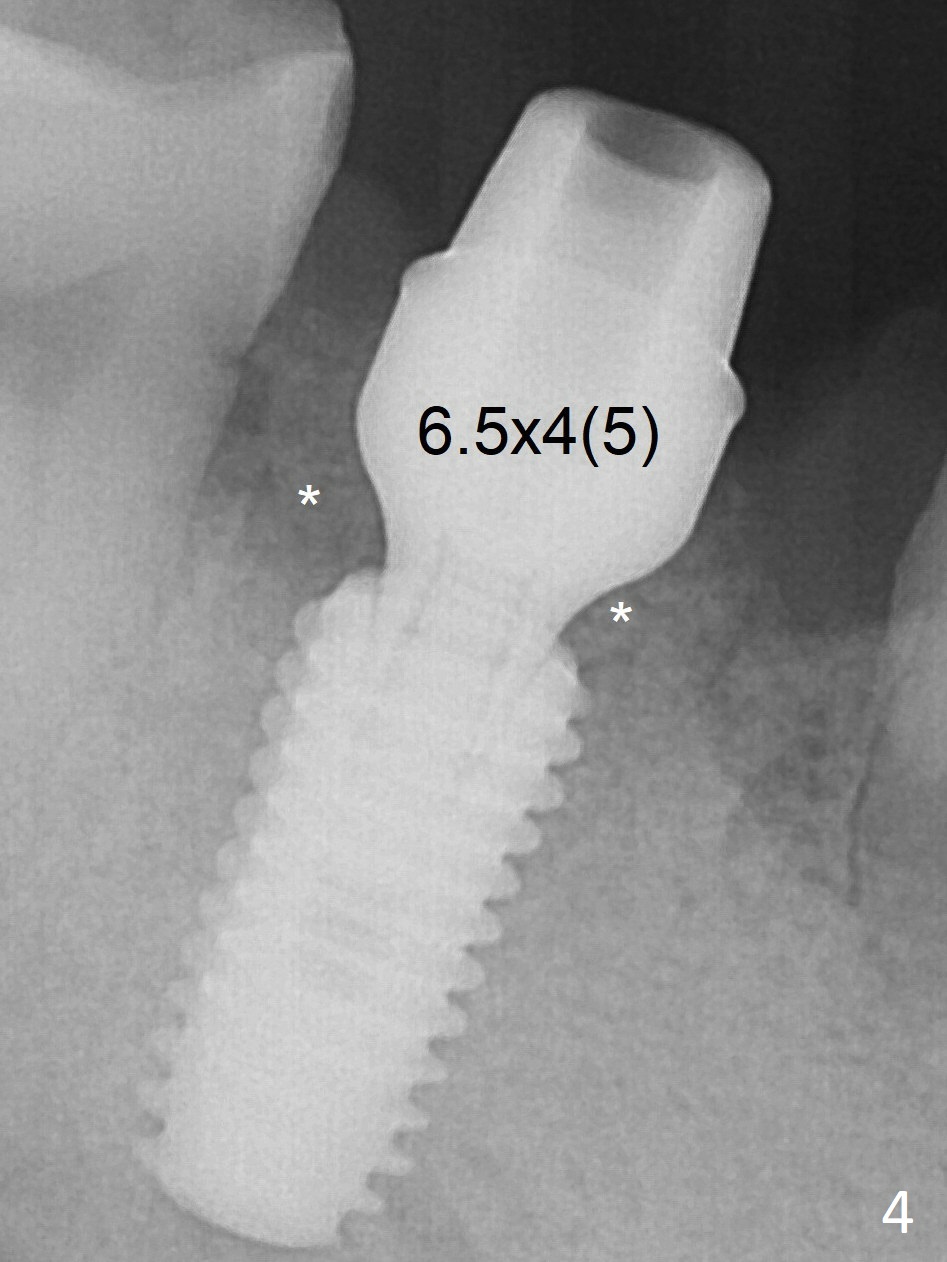

Following 4.8 mm drill, a 5.5x11.5 mm implant is placed initially (Fig.3) with an apical space (*) and clearance between the osteotomy and the Inferior Alveolar Canal (red dashed line). The implant is placed deeper with placement of a 6.5x4(5) mm abutment and bone graft (*, Fig.4). There is no bone loss 3.5 months postop (Fig.8). The abutment margin is lowered by prep before impression. In fact the abutment has not been seated completely since its placement (Fig.4,5,8).